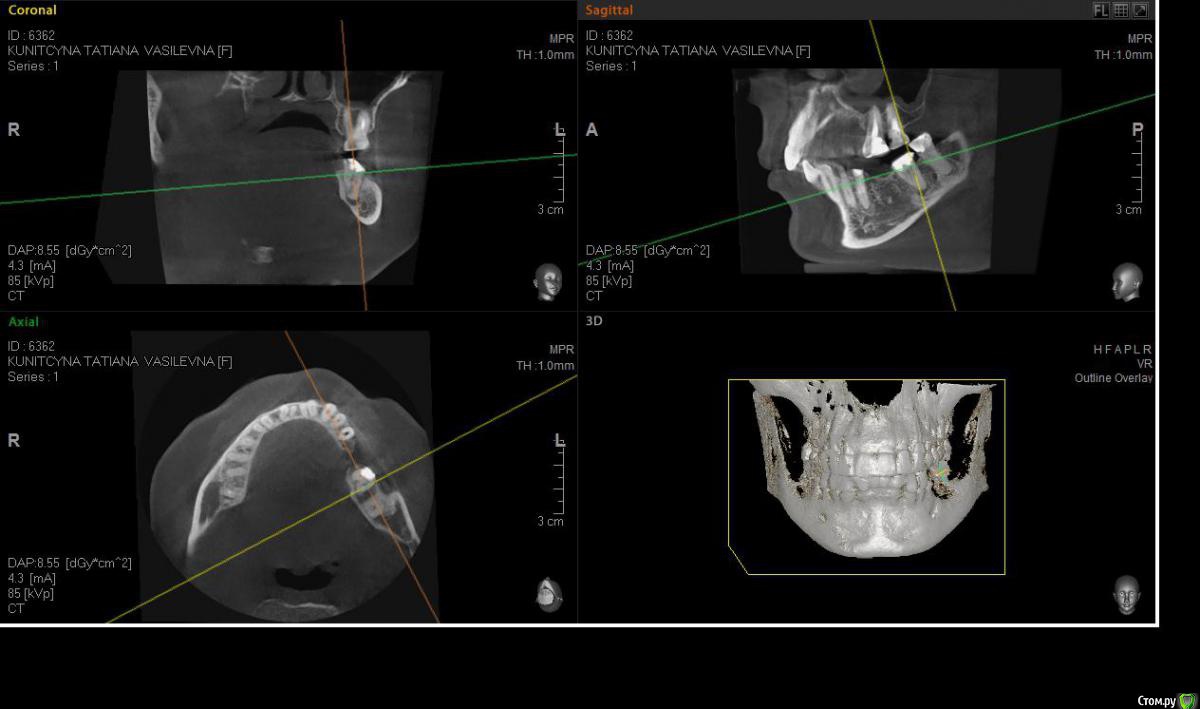

denis1987 Опубликовано 6 декабря, 2014 Поделиться Опубликовано 6 декабря, 2014 (изменено) Планирую удаление зуба 37 + имплантация в область отсутствующего 36. Думал поставить одномоментно в область 37, но пугает близость костного дефекта к язычной кортикалке и близость н.ч канала. Изменено 6 декабря, 2014 пользователем denis1987 Ссылка на комментарий

denis1987 Опубликовано 6 декабря, 2014 Автор Поделиться Опубликовано 6 декабря, 2014 Думаю тоже отсроченно делать , так как если ось импланта стараться располагать в направлении преддверия, то есть риск и повреждения нижнечелюстного канала. Ссылка на комментарий

kriokov Опубликовано 6 декабря, 2014 Поделиться Опубликовано 6 декабря, 2014 я бы поставил отсрочено так же. Корни 37 сходятся, перегородки нет совсем, направление так себе. Имхо Ссылка на комментарий

lonely_jack Опубликовано 10 декабря, 2014 Поделиться Опубликовано 10 декабря, 2014 (изменено) Ось на кт выставляйте по 5 зубу и смотрите нет ли наклона 7 зуба в сторону отсутствующего. Если наклон присутствует, то и картинка среза будет более "радостная". Недавно схожий случай был, установил одномоментно. У вашего пациента наклон, похоже, есть Изменено 10 декабря, 2014 пользователем lonely_jack Ссылка на комментарий